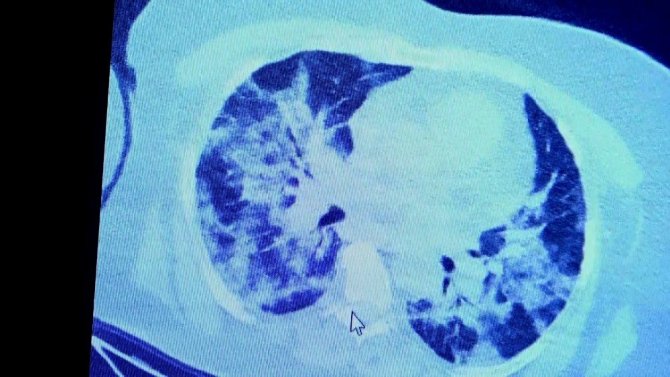

VM Medical Park Samsun Hastanesi'nde görev yapan Göğüs Hastalıkları Kliniği'nden Prof. Dr. Şevket Özkaya da bir hafta ilaç kullanmayan bir pozitif hastanın akciğer tomografisini inceledi. Hasta pozitif haldeyken ilk akciğer tomografisine bakıldı. Tomografide akciğerlerdeki tutulmanın az olduğu gözlemlendi. Akabinde aynı hastanın verilen ilaçları kullanmamış ve 1 hafta boyunca tedaviye uymamış haldeki akciğer tomografisine bakıldı. Sonuç ise ilaç kullanımının önemini ortaya çıkardı. Hastanın akciğer tomografisinde yaygın buzlu camların ve hava yollarının hava yerine ciddi şekilde sıvı ile dolduğu gözlemlendi.

Akciğer tomografisinde oluşan değişim ile ilgili bilgi veren Prof. Dr. Şevket Özkaya, "Ekranda 55 yaşında bir kadın hastamızın filmini görüyorsunuz. Bu kadın hastamız acil servisimize ateş şikâyetiyle geldi ve korona virüsünden şüphe ettik. Testini yaptığımızda ise testin sonucu pozitif geldi. Tomografi çektiğimiz zaman akciğerlerinde henüz ciddi bir tutulum görünmezken hastamız 55 yaşında olduğu için her an ilerleyebilir korkusuyla Sağlık Bakanlığımızın önerdiği ilaçları ve reçeteyi hastanemizden kendisine verdik. Hasta kendini evde karantinaya aldı fakat sonradan öğrendik ki tereddüt ettiği için ilaçlarını kullanmayarak kendini evde tedavisiz bırakmış. Yaklaşık bir hafta sonra aynı hasta acil servisimize bu sefer solunum yetmezliği şikâyetiyle geldi. Solunum yetmezliği gelişince hastanın akciğer tomografisinde "buzlu cam" dediğimiz ve daha ileri konsolide alanların oluştuğunu gördük. Yaygın akciğer harabiyeti dediğimiz bir tablo oluşmuştu. Bu durumda hastada solunum yetmezliği olduğu için yoğun bakıma almak zorunda kaldık" dedi.